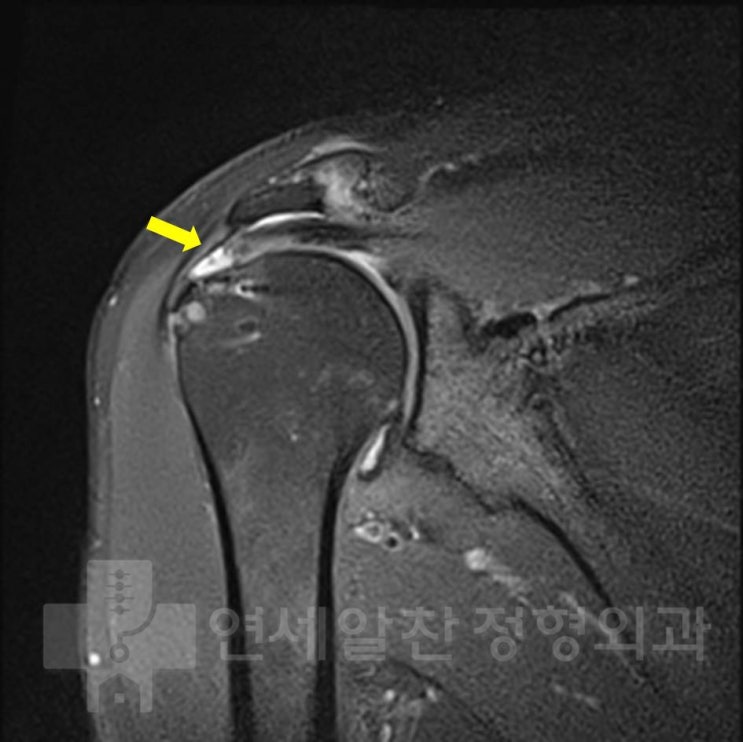

극상근 점액낭측 파열에서 이중교량형 봉합법을 이용한 수술의 결과

58세 여자환자로 3개월전 일하는 도중 발생한 어깨 통증을 주소로 본원으로 내원하였다. 타원에서 주사치료...